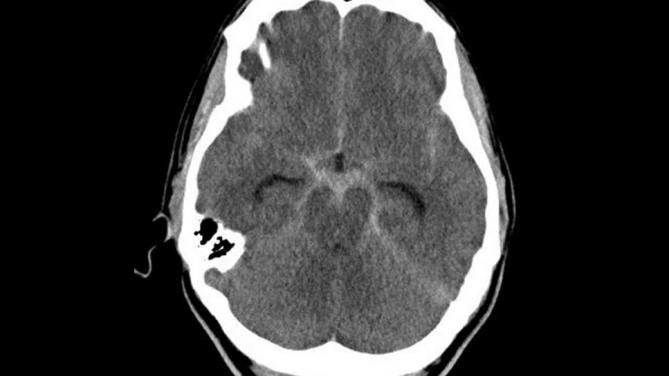

Assinale a alternativa correta a respeito da condição mostrada na imagem a seguir.

A maioria dos casos é causada por ruptura de aneurisma.